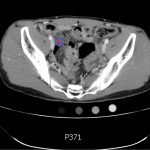

The CT abdomen/pelvis with intravenous contrast shows a dilated appendix (see red outline) with thickened, hyperenhancing wall (see blue outline) best visualized in the axial and coronal planes.